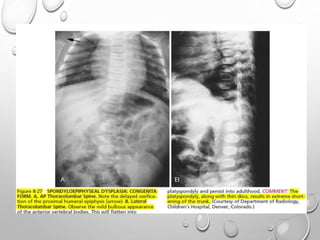

RADIOLOGY

VERTEBRAE

LUMBOTHORACIC KYPHOSIS

LUMBER HYPER LORDOSIS

LENGTH GENERALLY NORMAL

PLATYSPONDYLY , DISC HEIGHT EQ TO VERTEBRAL BODY

POSTERIOR SCALLOPING

PEDICLES ARE SORT , THICK , INTERPEDICULAR DISTANCE DECREASED

ANGULAR KYPHOSIS AT THORACOLUMBER JUNCTION RESULTING FROM

ANTERIOR BEAKING OR BULLET NOSE VERTEBRAE

SPINAL CANAL STENOSIS ---- PATHOLOGIC HALLMARK

• 1. DYSPLASTIC OR SQUARE

ILIAC BONES

2. NARROW SACRO-SCIATIC

NOTCHES

3. FLAT BILATERAL

ACETABULAR ROOFS

4. SHORT BOTH FEMORAL

NECKS

5. CHAMPAGNE GLASS-

SHAPED PELVIC CAVITY